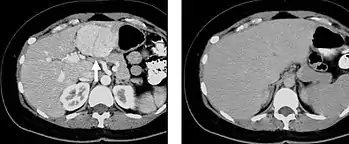

The late arterial phase is timed to correspond to the peak concentration of contrast material in highly vascular tumors and is performed approximately 20-35 seconds after the injection of intravenous contrast. Early arterial phase imaging is predominantly utilized for angiography and will be discussed separately. Late arterial phase imaging is almost always performed in conjunction with other phases (e.g. portal venous phase) to allow more complete characterization of any identified abnormalities (figure 4). The primary indication for a late arterial phase is for the evaluation of hypervascular tumors of the liver such as hepatocellular carcinoma or hypervascular metastases (figure 4). Typical hypervascular tumors for which this would be used include: hepatocellular carcinoma; renal cell carcinoma; melanoma; carcinoid/neuroendocrine tumors; some sarcomas; choriocarcinoma; and thyroid carcinoma. Although a “hypervascular”, biphasic evaluation would generally be used for these patients, note that a single phase is often adequate for follow up imaging.

Liver masses

When evaluating hepatic masses, it can be advantageous to have both late arterial and portal venous phase images (biphasic imaging, figure 4) since some tumors enhance briskly during the arterial phase (hepatocellular carcinoma, hepatic adenoma, follicular nodular hyperplasia (FNH), and hypervascular metastasis), but may be occult or difficult to characterize on portal venous phase imaging alone (figure 6). However, it should be stressed that the addition of late arterial phase images is only indicated if one of these tumors is suspected, or if there is a need for further characterization of a hepatic mass, since the large majority of patients will not benefit from the addition of this phase. In addition, if there is a need to definitively characterize a hepatic mass, MRI is generally more sensitive and specific, with no associated radiation dose.